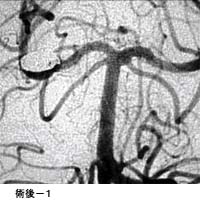

(3)頸動脈狭窄症に対するステント留置術

(現在、ステントは保険適応となっておりません。)